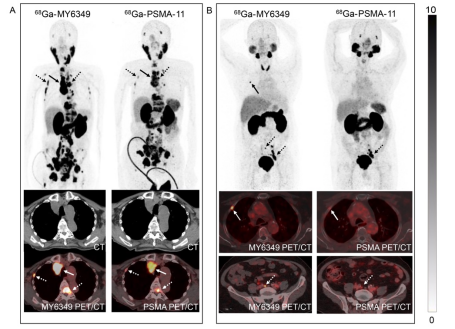

68Ga-MY6349 PET/CT與68Ga-PSMA-11 PET/CT在前列腺癌中的成像比較

我們將68Ga-MY6349與另一種經(jīng)FDA批準(zhǔn)的前列腺癌PET示蹤劑68Ga-PSMA-11進(jìn)行了頭對(duì)頭比較。在12例經(jīng)病理確診的前列腺癌患者中,68Ga-MY6349 PET/CT在原發(fā)及轉(zhuǎn)移病灶中表現(xiàn)出與68Ga-PSMA-11相似的顯像劑攝取,但在轉(zhuǎn)移病灶中表現(xiàn)出較68Ga-PSMA-11更高的靶/本底比(TBR),從而有利于檢測(cè)到更多的骨轉(zhuǎn)移病灶(病灶數(shù)目:122 vs. 101),并表現(xiàn)與68Ga-PSMA-11相當(dāng)?shù)牧馨徒Y(jié)轉(zhuǎn)移檢出率(病灶數(shù)目:61 vs. 60)。圖7展示了68Ga-MY6349 PET/CT相較于68Ga-PSMA-11 PET/CT優(yōu)越性的代表PET/CT病例。

圖7. 68Ga-MY6349 PET/CT和68Ga-PSMA-11 PET/CT在轉(zhuǎn)移性前列腺癌患者中的代表性圖像。(A)一名77歲男性前列腺癌患者,接受內(nèi)分泌治療后進(jìn)行PET/CT成像再分期。相比68Ga-PSMA-11,68Ga-MY6349 PET/CT顯示了更多的轉(zhuǎn)移病灶,并在淋巴結(jié)轉(zhuǎn)移(實(shí)箭頭)和骨轉(zhuǎn)移(虛箭頭)中具有更高的示蹤劑攝取(SUVmax 30-40)。(B)一名70歲男性患者,病理確診為前列腺癌,接受PET/CT進(jìn)行初始分期。68Ga-MY6349 PET/CT在右側(cè)肋骨轉(zhuǎn)移(實(shí)箭頭)和腹膜后微小轉(zhuǎn)移淋巴結(jié)(4mm,虛箭頭)中顯示出較68Ga-PSMA-11更高的示蹤劑攝取。